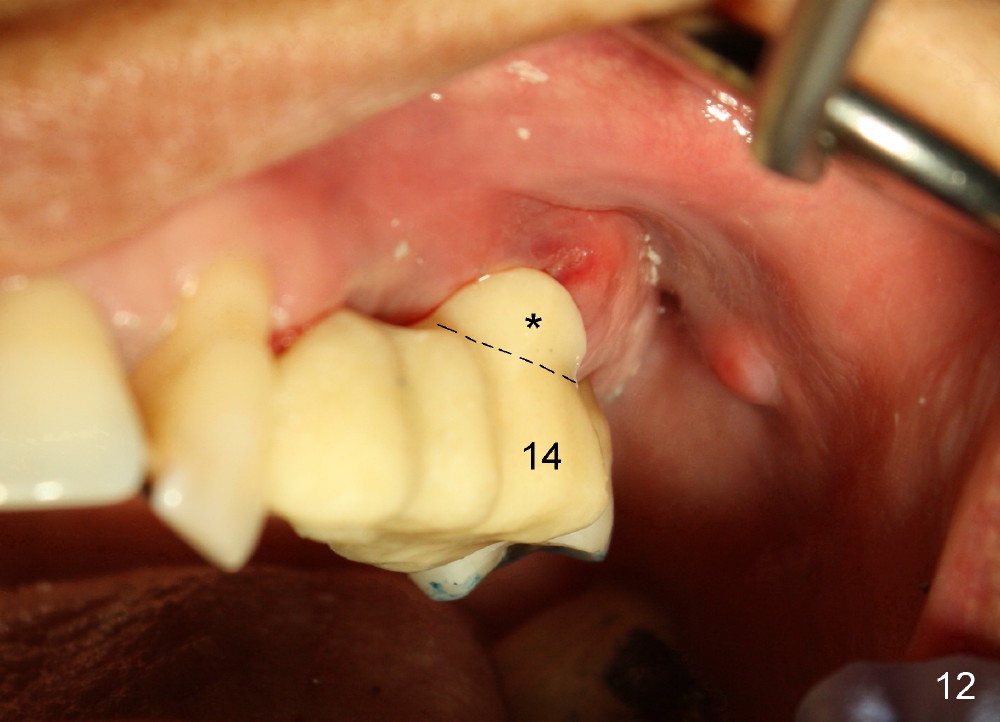

A 53-year-old lady has a failing bridge (Fig.1). There is severe bone loss around the buccal roots of #14 (*). Purulent discharge is from the gingival sulcus (Fig.2 <) with localized gingival erythema and edema (*). When the bridge is removed, the tooth #12 is found nonsalvageable (Fig.3,4). These two teeth are to be replaced by immediate implants (Fig.5). Although the sinus floor is low buccally (arrowheads), a 6x14 mm gingiva-level implant can be placed in the septum close to the palatal socket or in the palatal socket at the site of #14.

Buccal to #14 implant/abutment is a large defect, which is filled with allograft and Osteogen and covered by collagen membrane (Fig.9 M). The defect at the site of #12 is mesiopalatal, which is repaired in the same fashion (Fig.10: M). The collagen membrane is in turn protected by the "overhang" (extension) of the immediate provisional bridge (Fig.11,12 *). Once the wounds heal (Fig.13, 9 days postop), the extension is trimmed (Fig.14).